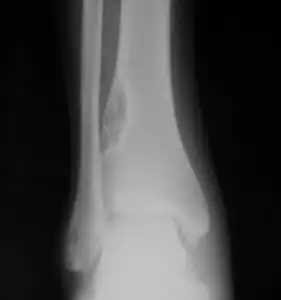

| X-ray of nonossifying fibroma of distal tibia. | |

Diagnosis is by X-ray or MRI, usually when investigating a person for something else.[3] Medical imaging typically shows a well marginated radiolucent lesion, with a distinct multilocular appearance, sometimes looking like bubbles.[3] It is usually around 1-2cm in size, but be as large as 7cm.[4] They consist of foci consist of collagen rich connective tissue, fibroblasts, histiocytes and osteoclasts.[3] Usually no treatment is required.[4] Surgical curettage and bone grafting may be required if it is large.[4]

It is usually iagnosed by x-ray or MRI, when investigating another problem.[1] The tumor presents as a well defined radiolucent lesion, with a distinct multilocular appearance, sometimes looking like a "soap bubble".[2] If small and no symptoms, then biopsy is not needed.[1]

1. a. Front view X-ray: NOF of the lower leg bone near ankle, with well-defined tumor

1. b. Side view X-ray: NOF of the lower leg bone near ankle, with well-defined tumor